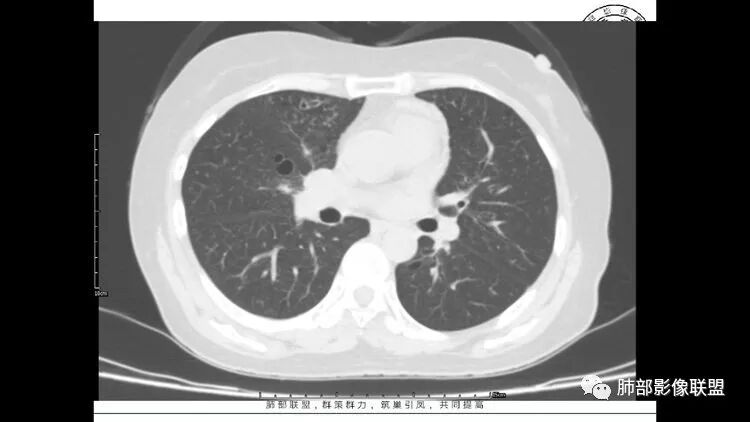

老年女性,眼炎入院,血常规正常,双肺多发囊状影,病变随机分布,形态单一,与血管关系密切,考虑LIP。左下肺混合GGO,边界尚清,贴近囊腔,鉴别腺癌。炎症指标无异常暂不考虑感染性病变。

胸CT:1.双肺多发囊性变,以中下肺为主,病变边缘可见肺动脉,部分囊内可见分隔及肺动脉,双下部分肺野周围可见小叶中心结节及树丫征。

2 左肺上叶尖后段 右肺上叶前段 右肺下叶外基底段 结节影,边界清楚,可见柔软毛刺,左肺下叶后基底段混合密度影。

3.纵隔淋巴结肿大?,以主动脉弓为界向上向下增大。

考虑:淋巴瘤肺浸润,眼部症状考虑与此有关;LIP?;继续鉴别肺腺癌?血管炎?。

LIP影像重要线索一句话:

双肺下叶分布为主的间质改变(磨玻璃影、小叶间隔增厚)、散在气囊影(常有血管贴边)、边界不清小结节